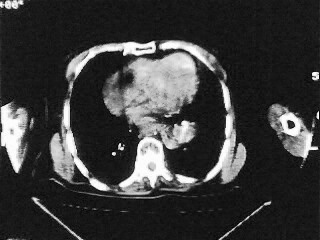

女,79,咳 嗽月余,无其它不适

1)两肺炎症。2)食管裂孔疝可能;建议行上消化道钡餐检查。

后纵隔内左心房至肝左叶后方椎体中线偏左巨大软组织包块,其壁均匀比较薄,其内可见宽气液平。

考虑食管裂孔疝。建议钡餐检查